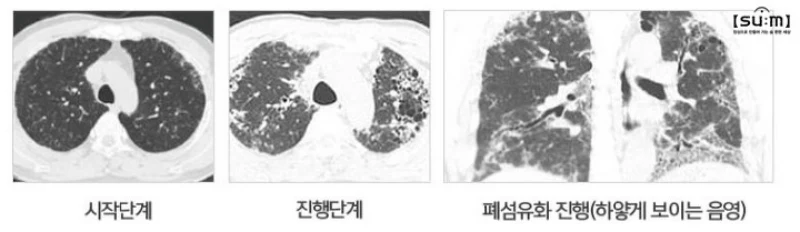

폐섬유증 진단

폐섬유증은 흉부 X-ray와 CT 검사를 통해 진단되며, 경우에 따라 흉강경을 통한 조직검사가 필요할 수 있습니다. 폐 기능 검사는 진행 정도를 파악하고 적절한 치료법을 결정하는데 중요합니다.